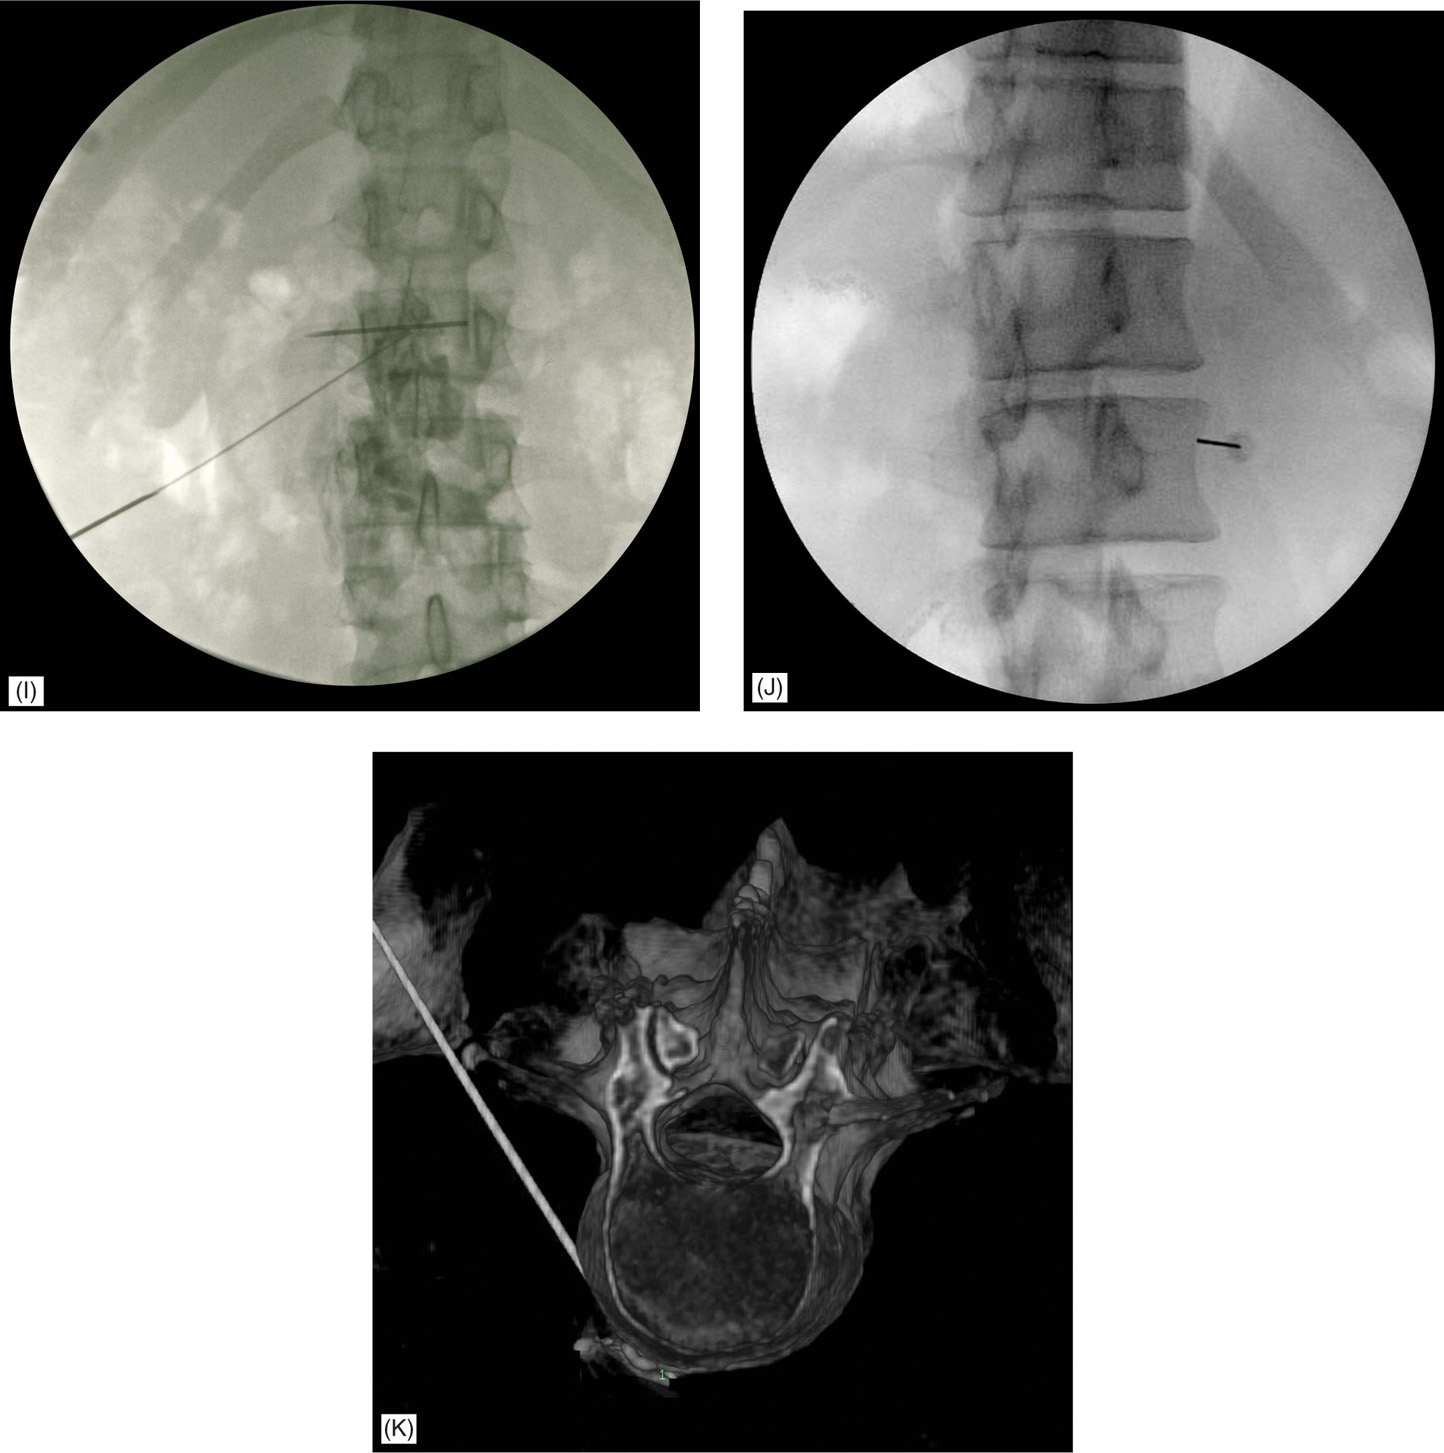

Lumbar Sympathetic Block Anesthesia Key Local Anesthesia Sympathetic Block Web techniques for diagnostic sbs include local anesthetic sympathetic blocks (lasbs), intravenous regional sympathetic. Web the sympathetic nervous system has been implicated in numerous pain syndromes ranging from neuropathic pain to vascular. Web local anaesthetic sympathetic blockade (lasb) is a common treatment for. Web sympathetic blocks are used in the diagnosis and treatment planning of patients with complex regional pain.. Local Anesthesia Sympathetic Block.

Lumbar Sympathetic Block Anesthesia Key Local Anesthesia Sympathetic Block Web local anaesthetic sympathetic blockade (lasb) is a common treatment for. Web sympathetic blocks are used in the diagnosis and treatment planning of patients with complex regional pain. Web techniques for diagnostic sbs include local anesthetic sympathetic blocks (lasbs), intravenous regional sympathetic. Web the sympathetic nervous system has been implicated in numerous pain syndromes ranging from neuropathic pain to vascular.. Local Anesthesia Sympathetic Block.

Lumbar Sympathetic Block Dr. Michael A. Castillo, MD Local Anesthesia Sympathetic Block Web sympathetic blocks are used in the diagnosis and treatment planning of patients with complex regional pain. Web the sympathetic nervous system has been implicated in numerous pain syndromes ranging from neuropathic pain to vascular. Web techniques for diagnostic sbs include local anesthetic sympathetic blocks (lasbs), intravenous regional sympathetic. Web local anaesthetic sympathetic blockade (lasb) is a common treatment for.. Local Anesthesia Sympathetic Block.

Complications of Lumbar Sympathetic Block Anesthesia Key Local Anesthesia Sympathetic Block Web local anaesthetic sympathetic blockade (lasb) is a common treatment for. Web the sympathetic nervous system has been implicated in numerous pain syndromes ranging from neuropathic pain to vascular. Web techniques for diagnostic sbs include local anesthetic sympathetic blocks (lasbs), intravenous regional sympathetic blockade (irsb), and systemic alpha. Web techniques for diagnostic sbs include local anesthetic sympathetic blocks (lasbs), intravenous. Local Anesthesia Sympathetic Block.